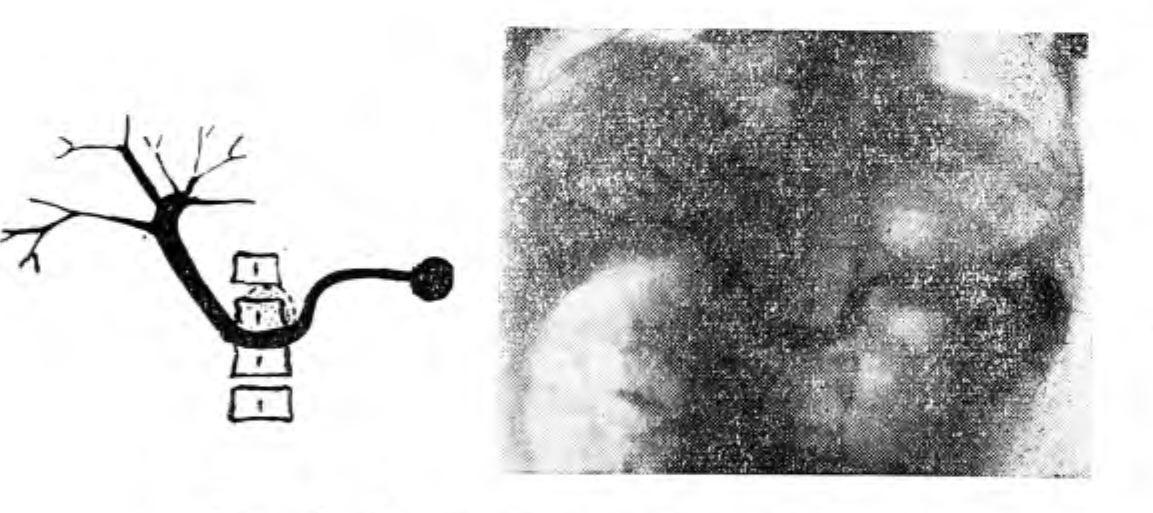

Приводим пример. К-, 50 лет, поступил 13/1-60 г. с диагнозом «рак антрального отдела и тела желудка». 23/1 — спленопортография: селезеночная, воротная вены и внутрипеченочные разветвления с четкими контурами, без видимых изменений (рис. 1). На 7-й секунде получена нормальная гепатограмма (фаза капиллярного гомогенного контрастирования печени).

Рис. 1. Нормальная спленопортограмма.